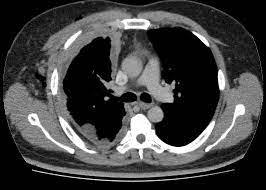

Quimioterapia con o sin decorticación con pleurectomía extendida para el mesotelioma

En pacientes con con mesotelioma pleural resecable la quimioterapia asociada con una decorticación con pleurectomía extendida se asoció con una peor supervivencia a 2 años y eventos adversos más graves que la quimioterapia sola. The Lancet Respiratory Medicine 10 de mayo de 2024.